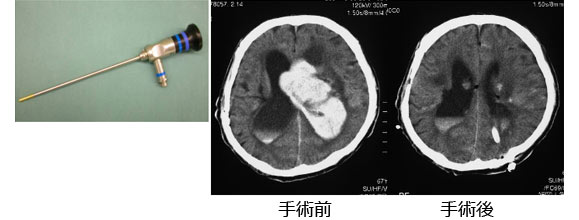

(2)内視鏡手術

この方法は全身麻酔で行います。右のような内視鏡を使ってテレビモニターなどで観察しながら血腫を摘出していきます。64歳の患者さんで左脳出血です。左後頭部に穴をあけて、内視鏡で血腫を摘出しました。左が手術前で、右が手術後のCTです。最近は、このような手術が主流になりつつあります。